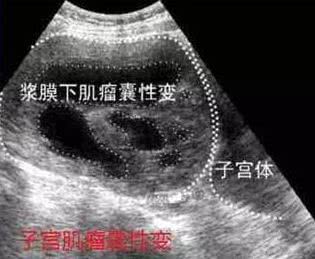

四、囊性变

囊性变或称假囊性变,往往是透明变性的进一步发展,偶尔可继坏死后发生,但亦可独自发展而成。

常在透明变性区域,因透明变性易于液化,形成大小不等的囊腔,腔内充满草黄色清亮的液体或血性液,囊腔可融合成大囊,致使肌瘤质地变软呈囊性。有人认为是黏液变性的进一步发展,形成的囊性变,腔隙内由清液或血性液代替黏液,并融合成大囊。